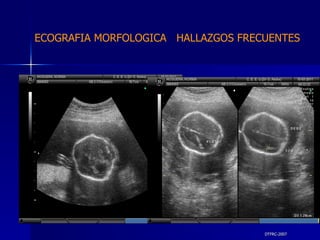

DTFRC-2007 ECOGRAFIA MORFOLOGICA  HALLAZGOS FRECUENTES   GENITOURINARIA DISPLASIA RENAL MULTIQUISTICA  3 HIDRONEFROSIS  2 QUISTE DE OVARIO FETAL  1 SISTEMA DIGESTIVO DILATACION INTESTINAL  2  SISTEMA ESQUELETICO   PIE BOT  2  20 % 6 % 6 %

DTFRC-2007 VALOR DIAGNOSTICA DE LA ECOGRAFIA MORFOLOGICO EN  MALFORMACIONES ABDOMINALES HIDRONEFROSIS 100 % VALVULAS URETRALES 100 %  RIÑONES POLIQUISTICOS  91 % AGENESIA RENAL 85 % PROTOCOLO  DE ESTUDIO  ECOGRAFICO DE LA ANATONIA  FETAL